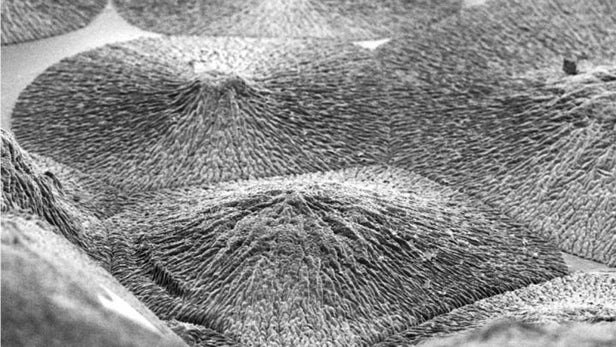

توریست مالزی- دانشمندان بریتانیایی روشی برای رشد مصنوعات مواد معدنی کشف کردند که میتواند موادی مشابه استخوان و مینای دندان پرورش دهد. یک گروه از محققان به رهبری دانشمندان دانشگاه کوئین ماری لندن، روشی جدید برای رشد مواد معدنی مصنوعی را کشف کردهاند که میتواند منجر به تولید بافتهای سخت بدن مانند استخوان شود.

این پیشرفت هیجانانگیز حکایت از آینده احیا کننده پزشکی دارد که در آن پزشکان میتوانند بافتهای سخت مانند مینای دندان و استخوان را رشد دهند. پوشش مینا که ما روی دندانهای خود داریم، یک ماده بسیار معدنی است که فوقالعاده قوی است. حفظ پوشش مینای دندان یکی از بزرگترین چالشهای دندانپزشکی مدرن است، زیرا میتواند طول عمر فرد را کاهش دهد و همچنین یکی از بافتهای بدن است که نمیتوان آن را بازسازی کرد و بدن نیز نمیتواند آن را بازیابی کند.

دانشمندان همواره مشغول بررسی انواع اهداف جالب توجه هستند که بتواند سبب بازسازی بافتهای سخت شود. اما آخرین پیشرفت، یک روش متفاوت است. استفاده از مواد پروتئینی که میتواند رشد نانوبلورهای آپاتیت را به نحوی که به لحاظ ساختاری مشابه مینای دندان باشد، میسر کند. این بدان معنی است که محققان میتوانند یک نانومواد مصنوعی را طوری کنترل کنند که به ایجاد ساختارهای مصنوعی که میتوانند رفتار انواع مختلفی از بافتهای سخت را تقلید کند، منجر شود.

دانشمندان همواره مشغول بررسی انواع اهداف جالب توجه هستند که بتواند سبب بازسازی بافتهای سخت شود. اما آخرین پیشرفت، یک روش متفاوت است. استفاده از مواد پروتئینی که میتواند رشد نانوبلورهای آپاتیت را به نحوی که به لحاظ ساختاری مشابه مینای دندان باشد، میسر کند. این بدان معنی است که محققان میتوانند یک نانومواد مصنوعی را طوری کنترل کنند که به ایجاد ساختارهای مصنوعی که میتوانند رفتار انواع مختلفی از بافتهای سخت را تقلید کند، منجر شود.